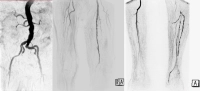

Filmbeispiel

- subtotale Stenosen der A. femoralis superficialis links

- Verschluss der A. poplitea Abschnitt I – III

- Teilverschlüsse aller Unterschenkelarterien

- Verschluss des primären und sekundären Fußbogens

Z.n. femoro-poplitealem Venenbypass rechts, autologe V. saphena magna verbraucht, links zu kaliberschwach → alloplastischer Bypass.